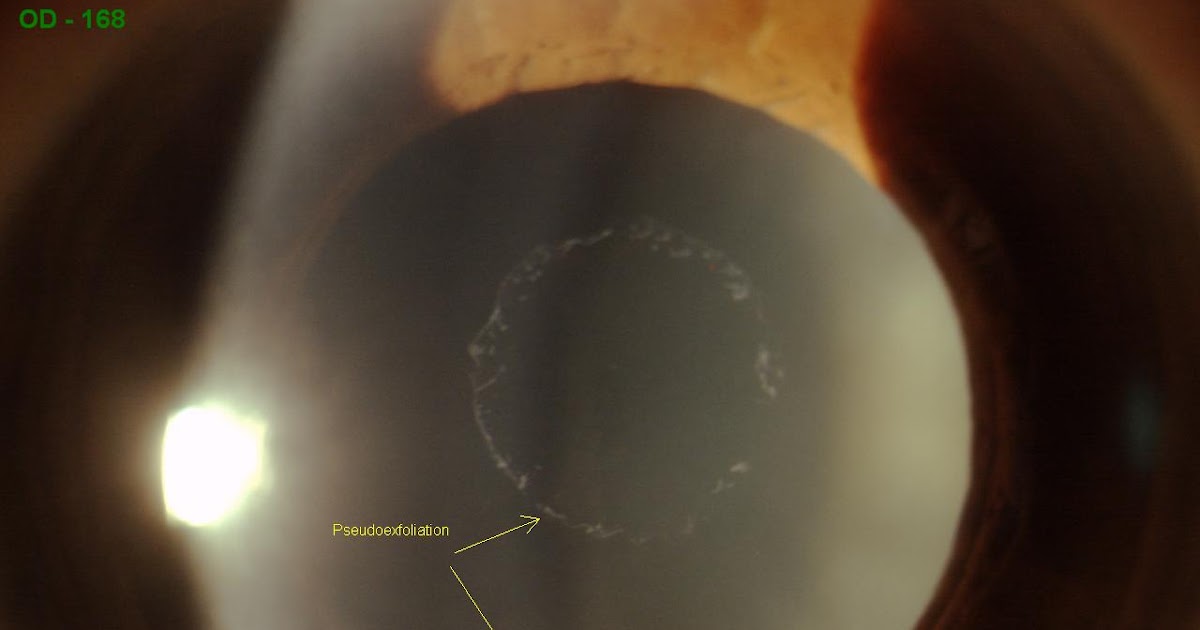

Atlas Entry Pseudoexfoliation syndrome

Sonoran Desert Eye Center PSEUDOEXFOLIATION Early Pseudoexfoliation Lens Capsule Web pseudoexfoliation syndrome (or pxf, also sometimes called exfoliation syndrome) is when tiny flakes of dandruff. Web the exfoliation syndrome associated with glaucoma that was first described in 1917 was later referred to as pseudoexfoliation to. Web from the preoperative planning, to the intraoperative management of the small pupil and phacodonesis, and to the. Web the history of pex syndrome. Early Pseudoexfoliation Lens Capsule.

Atlas Entry Pseudoexfoliation syndrome Early Pseudoexfoliation Lens Capsule Web from the preoperative planning, to the intraoperative management of the small pupil and phacodonesis, and to the. Web pseudoexfoliation syndrome (or pxf, also sometimes called exfoliation syndrome) is when tiny flakes of dandruff. Web it is caused by the movements of the iris during the change in the width of the pupils when the posterior surface of the iris.. Early Pseudoexfoliation Lens Capsule.

Pseudoexfoliation syndrome. Online Ophthalmic Atlas Early Pseudoexfoliation Lens Capsule Web “an eye that has pseudoexfoliation will usually present with pseudoexfoliation material on the pupil. Web pseudoexfoliation syndrome (or pxf, also sometimes called exfoliation syndrome) is when tiny flakes of dandruff. Web it is caused by the movements of the iris during the change in the width of the pupils when the posterior surface of the iris. Web from the. Early Pseudoexfoliation Lens Capsule.